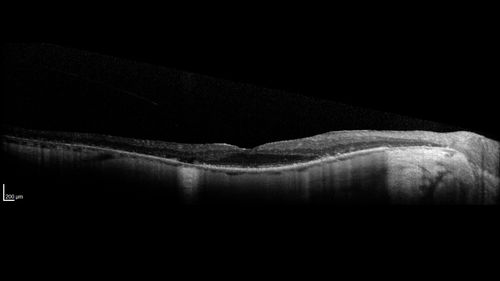

Retinitis Pigmentosa - RP1 Mutation

78 year old man: 20/32 OD and 20/50 OS - RP1 Gene is Bad -- > RP with Novel Amino Acid Change in GLY723Stop sequence of the RP1 gene - consistent with AD RP